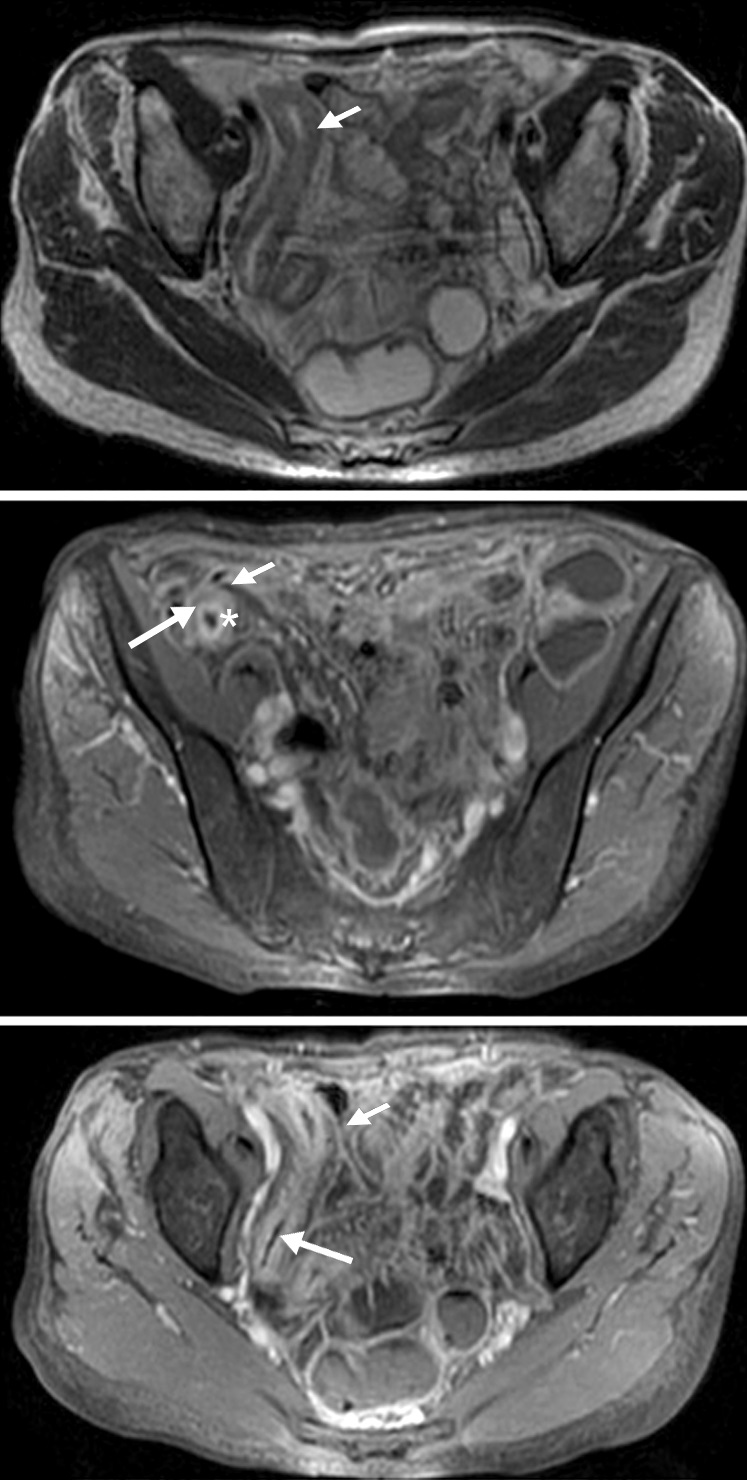

Figura 5

Enfermedad de Crohn

a y b) Secuencias T2 con saturación grasa en el

plano axial. Engrosamiento parietal circunferencial

de la última asa ileal sin edema que contacta con

el colon transverso presentando adherencias con

el mismo (flecha). Tracto sinusal que se extiende

desde el asa alterada al borde anterior del músculo

ilíaco derecho (flecha corta).

c) Secuencia T1 con

saturación grasa y gadolinio, pequeña colección

líquida en el espesor muscular con realce parietal

(punta de flecha)